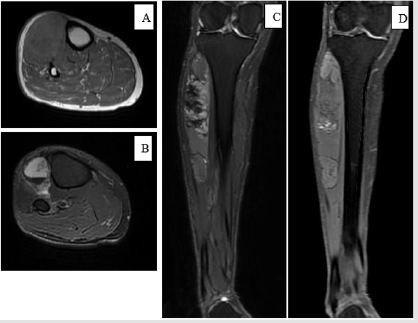

A 60-year old female kicked on the motor vehicle with the right lower extremity and developed mild pain at the right calf in September 2017. Five months later, without improvement in her symptoms and persistent swelling in the lateral aspect of calf, she came to the out-patient department (OPD) in Kaohsiung Medical University Hospital. Physical exam revealed pain to palpitation and slight swelling of right lateral calf. Based on the trauma history with no other specific findings, the physician diagnosed a muscle sprain with concomitant bleeding and treated her with pain medication. For further survey of prolonged leg swelling, an MRI was obtained weeks later that showed multilobulated mass (about 16 x 4cm) in anterior tibialis muscle, heterogeneous signal intensity on both T1 and T2 weighted images. Both the radiologist and the attending physician interpreted the MRI as intramuscular hematoma with multiple stages. So conservative care with continued physical therapy was recommended. Three months later, the mass continued to increase in size and symptoms became worsened. The patient visited our OPD again and was thus referred to the Orthopedic oncology surgeon for evaluation. Clinical exam showed a 18 x 4.5cm, firm, irregular, immobile mass extending from the anterior to the lateral aspect of right calf (Figure 1).

Figure 2a: (First MRI, A: axial T1-weighted, B: axial T2-weighted, C: coronal T1-weighted, D: coronal T2-weighted).

Note: A 60-year-old female developed a painful lump at the anterolateral side of calf after minor trauma. MRI revealed intramuscular hematoma with multiple stage and no evidence of bone and fascia invasion.